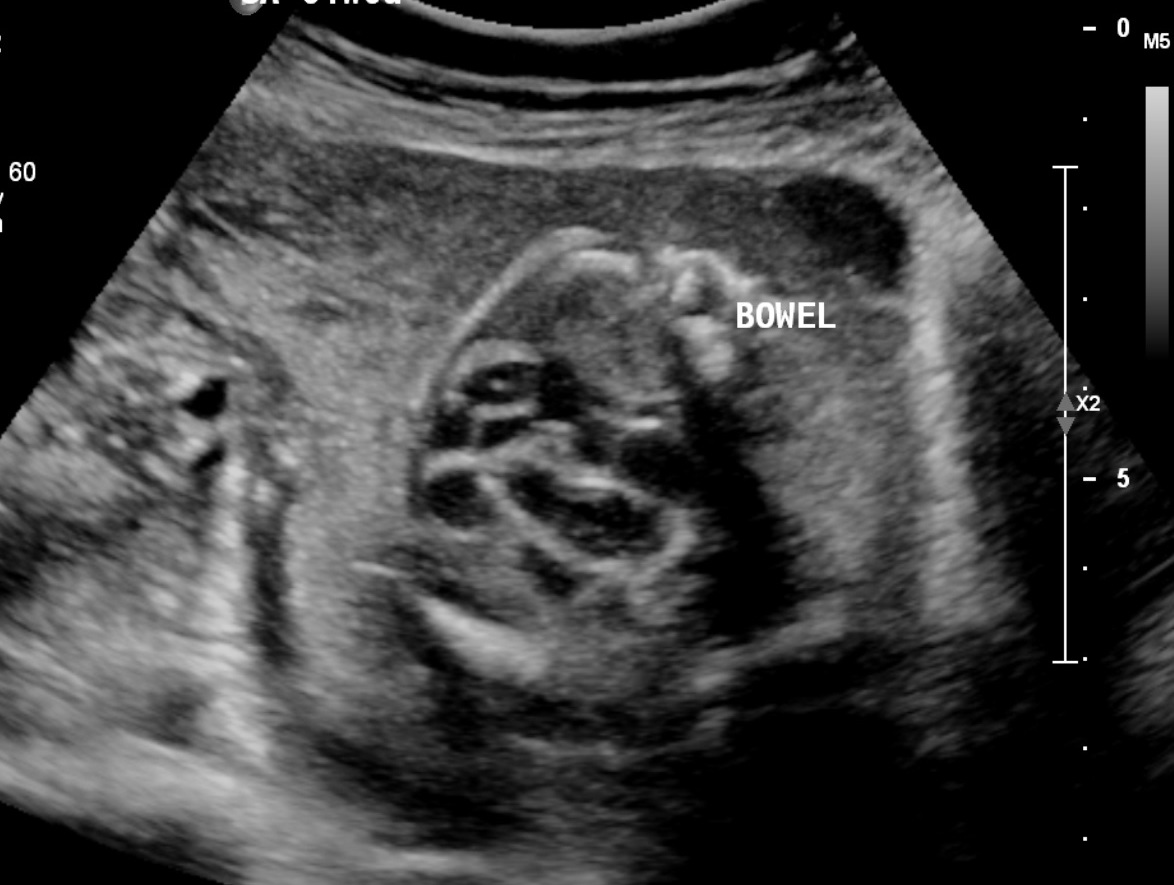

A two-vessel cord can be diagnosed during pregnancy through ultrasound examinations. If a two-vessel cord is suspected, the healthcare provider may recommend additional testing, such as:

- Umbilical artery Doppler: This test measures the blood flow through the umbilical arteries.